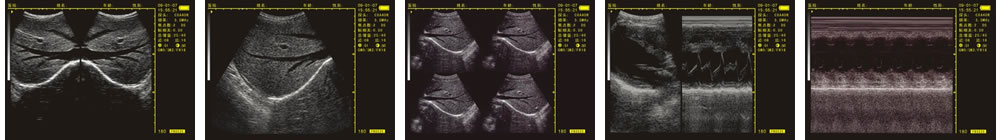

優(yōu)質(zhì)的成像效果

V-20掌上B型超聲診斷儀(動(dòng)物版)一流的數(shù)字成像技術(shù),圖像更清晰